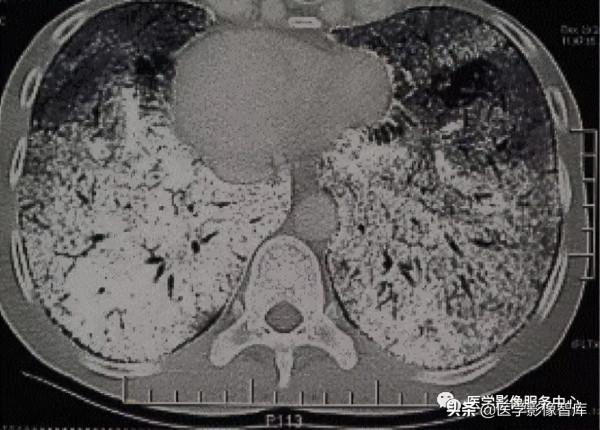

⻢賽克徵:⻢賽克徵是指肺HRCT中出現的⼩葉或多⼩葉分佈的密度減低區域和正常肺之間形成⿊⽩相間的影像。它的名字來源於“⻢賽克”這個詞,這個詞描述了不同的⽯頭或瓷磚組成的構圖,圖14。

⻢賽克徵可以在三種主要的肺疾病中發現:⼩⽓道疾病、⾎管性肺疾病和浸潤性肺疾病。在慢性⾎栓性肺疾病等⾎管疾病中,在低密度區⾎管的⼤⼩和數量很少,使⽤的術語是“⻢賽克灌注”(圖13A, 13B)。在⼩⽓道疾病如閉塞性細⽀⽓管炎中,在低衰減區存在“⻢賽克灌注”,這些區域在呼⽓時的胸部CT掃描中表現低密度的⻢賽克,⽽在吸⽓相正常,提示⼩葉空⽓滯留(圖13C, 13D)。浸潤性疾病可表現⻢賽克徵,滲出的GGO與周圍正常肺組織相⽐,它們有更⾼的密度,⾼密度GGO與周圍相對低的正常肺組織的形成⿊⽩相間的⻢賽克徵。浸潤性疾病⻅於耶⽒肺孢⼦菌肺炎(圖 13E)、慢性嗜酸性肺炎、過敏性肺炎和隱源性組織肺炎等。